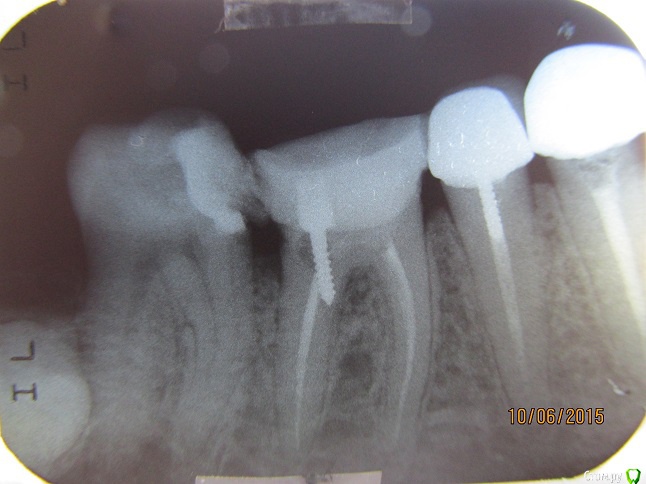

Борис Ф Опубликовано 11 июня, 2015 Поделиться Опубликовано 11 июня, 2015 (изменено) Имеем 6-й нижний зуб справа. У зуба практически не было коронки, но корень был здоров. Сделали мне т. н. "восстановление зуба с армирующими штифтами и светоотверждаемым материалом" с целью дальнейшей постановки коронки. За время, пока стоматолог делала мне зуб, я так и не понял, поставила ли она штифт. Я всегда этот момент замечаю, т. к. штифт вкручивают, и это чувствуется. Я заподозрил, что врач не поставила штифт вообще. Я сделал в другой клинике рентген отремонтированного зуба, и у меня появились вопросы. 1. Сколько штифтов обычно ставится в двухкорневой зуб? 2. Штифт стоит не в канале. Нормально ли это? 3. Штифт стоит с одного боку абы как. Выполняет ли он при этом армирующую функцию? 4. Вокруг штифта, особенно ближе к коронке, имеется область разрежения. Не означает ли это, что штифт просто вставлен в заранее просверленное отверстие без вкручивания? 5. Сформированная вновь коронка зуба вплотную прижата к соседним зубам. Как в отсутствие зазора ставить на зуб коронку? 6. Ночью зуб начал болеть. Нормально ли это? Прошу уважаемых врачей по возможности ответить на мои вопросы. Первый снимок - после лечения, второй - до. Изменено 11 июня, 2015 пользователем Борис Ф Ссылка на комментарий

Гарриевич Опубликовано 12 июня, 2015 Поделиться Опубликовано 12 июня, 2015 по теменайдите адекватного стоматолога и решайте вопросуже сейчас дистальная (задняя) сторона зуба разрушена практически на уровне кости 1 Ссылка на комментарий